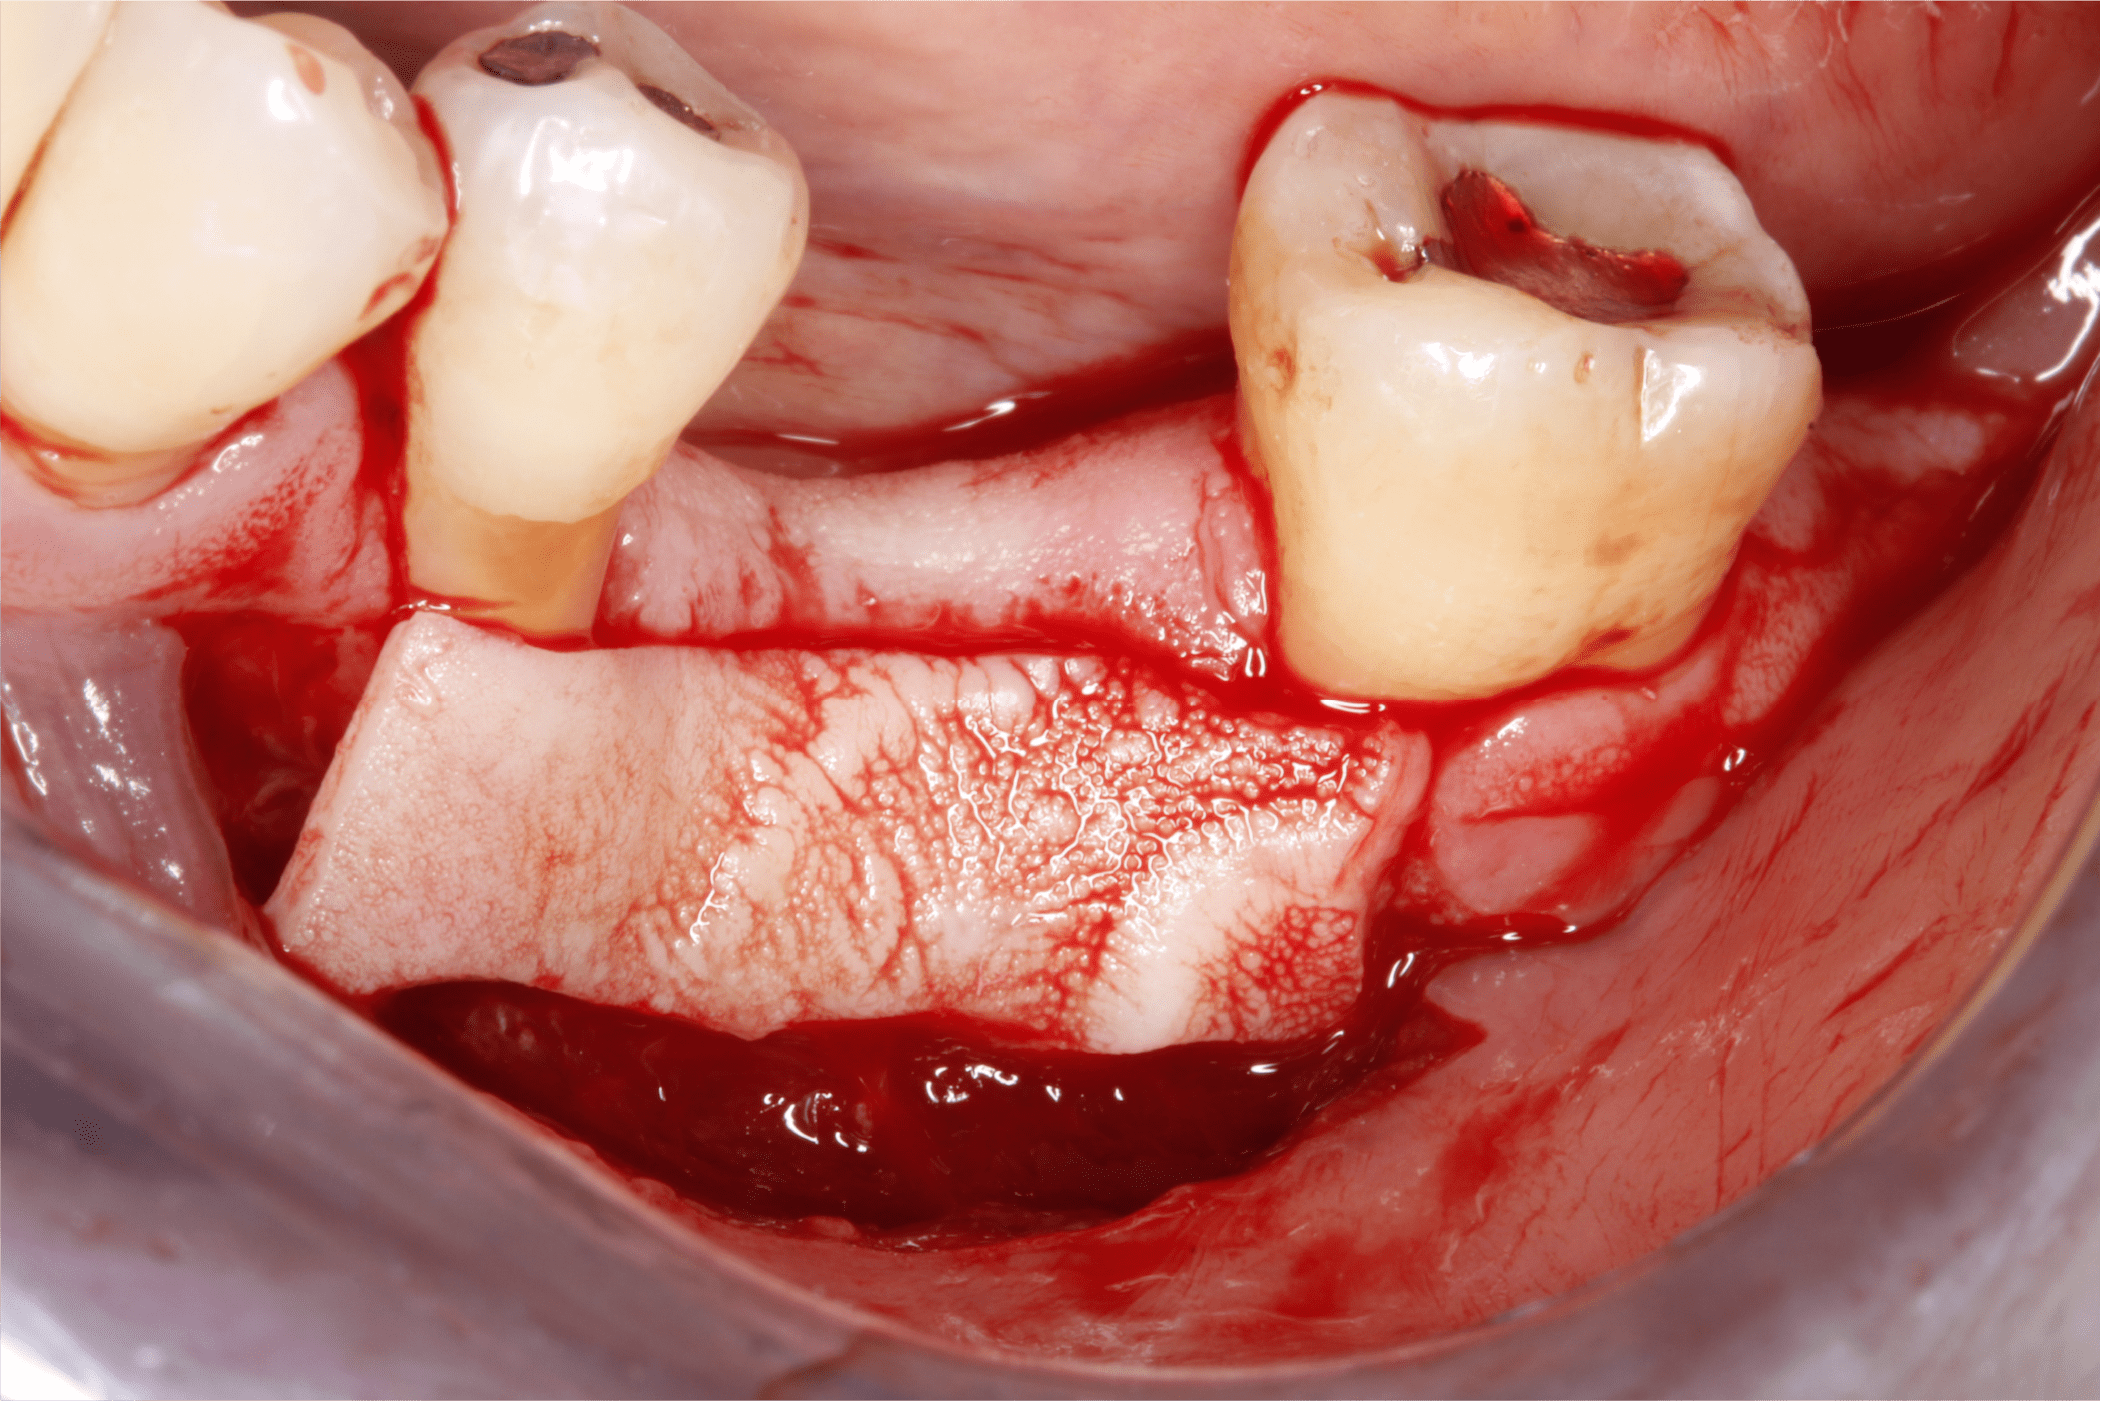

Una vez tomado el injerto epitelial se posicionó en el sitio receptor previamente preparado, se fijó con puntos simples en sus extremos y en la porción media se fijó con puntos colchoneros horizontal y cruzado (Fig. 9 y 10).

Fig. 9

Fig. 10